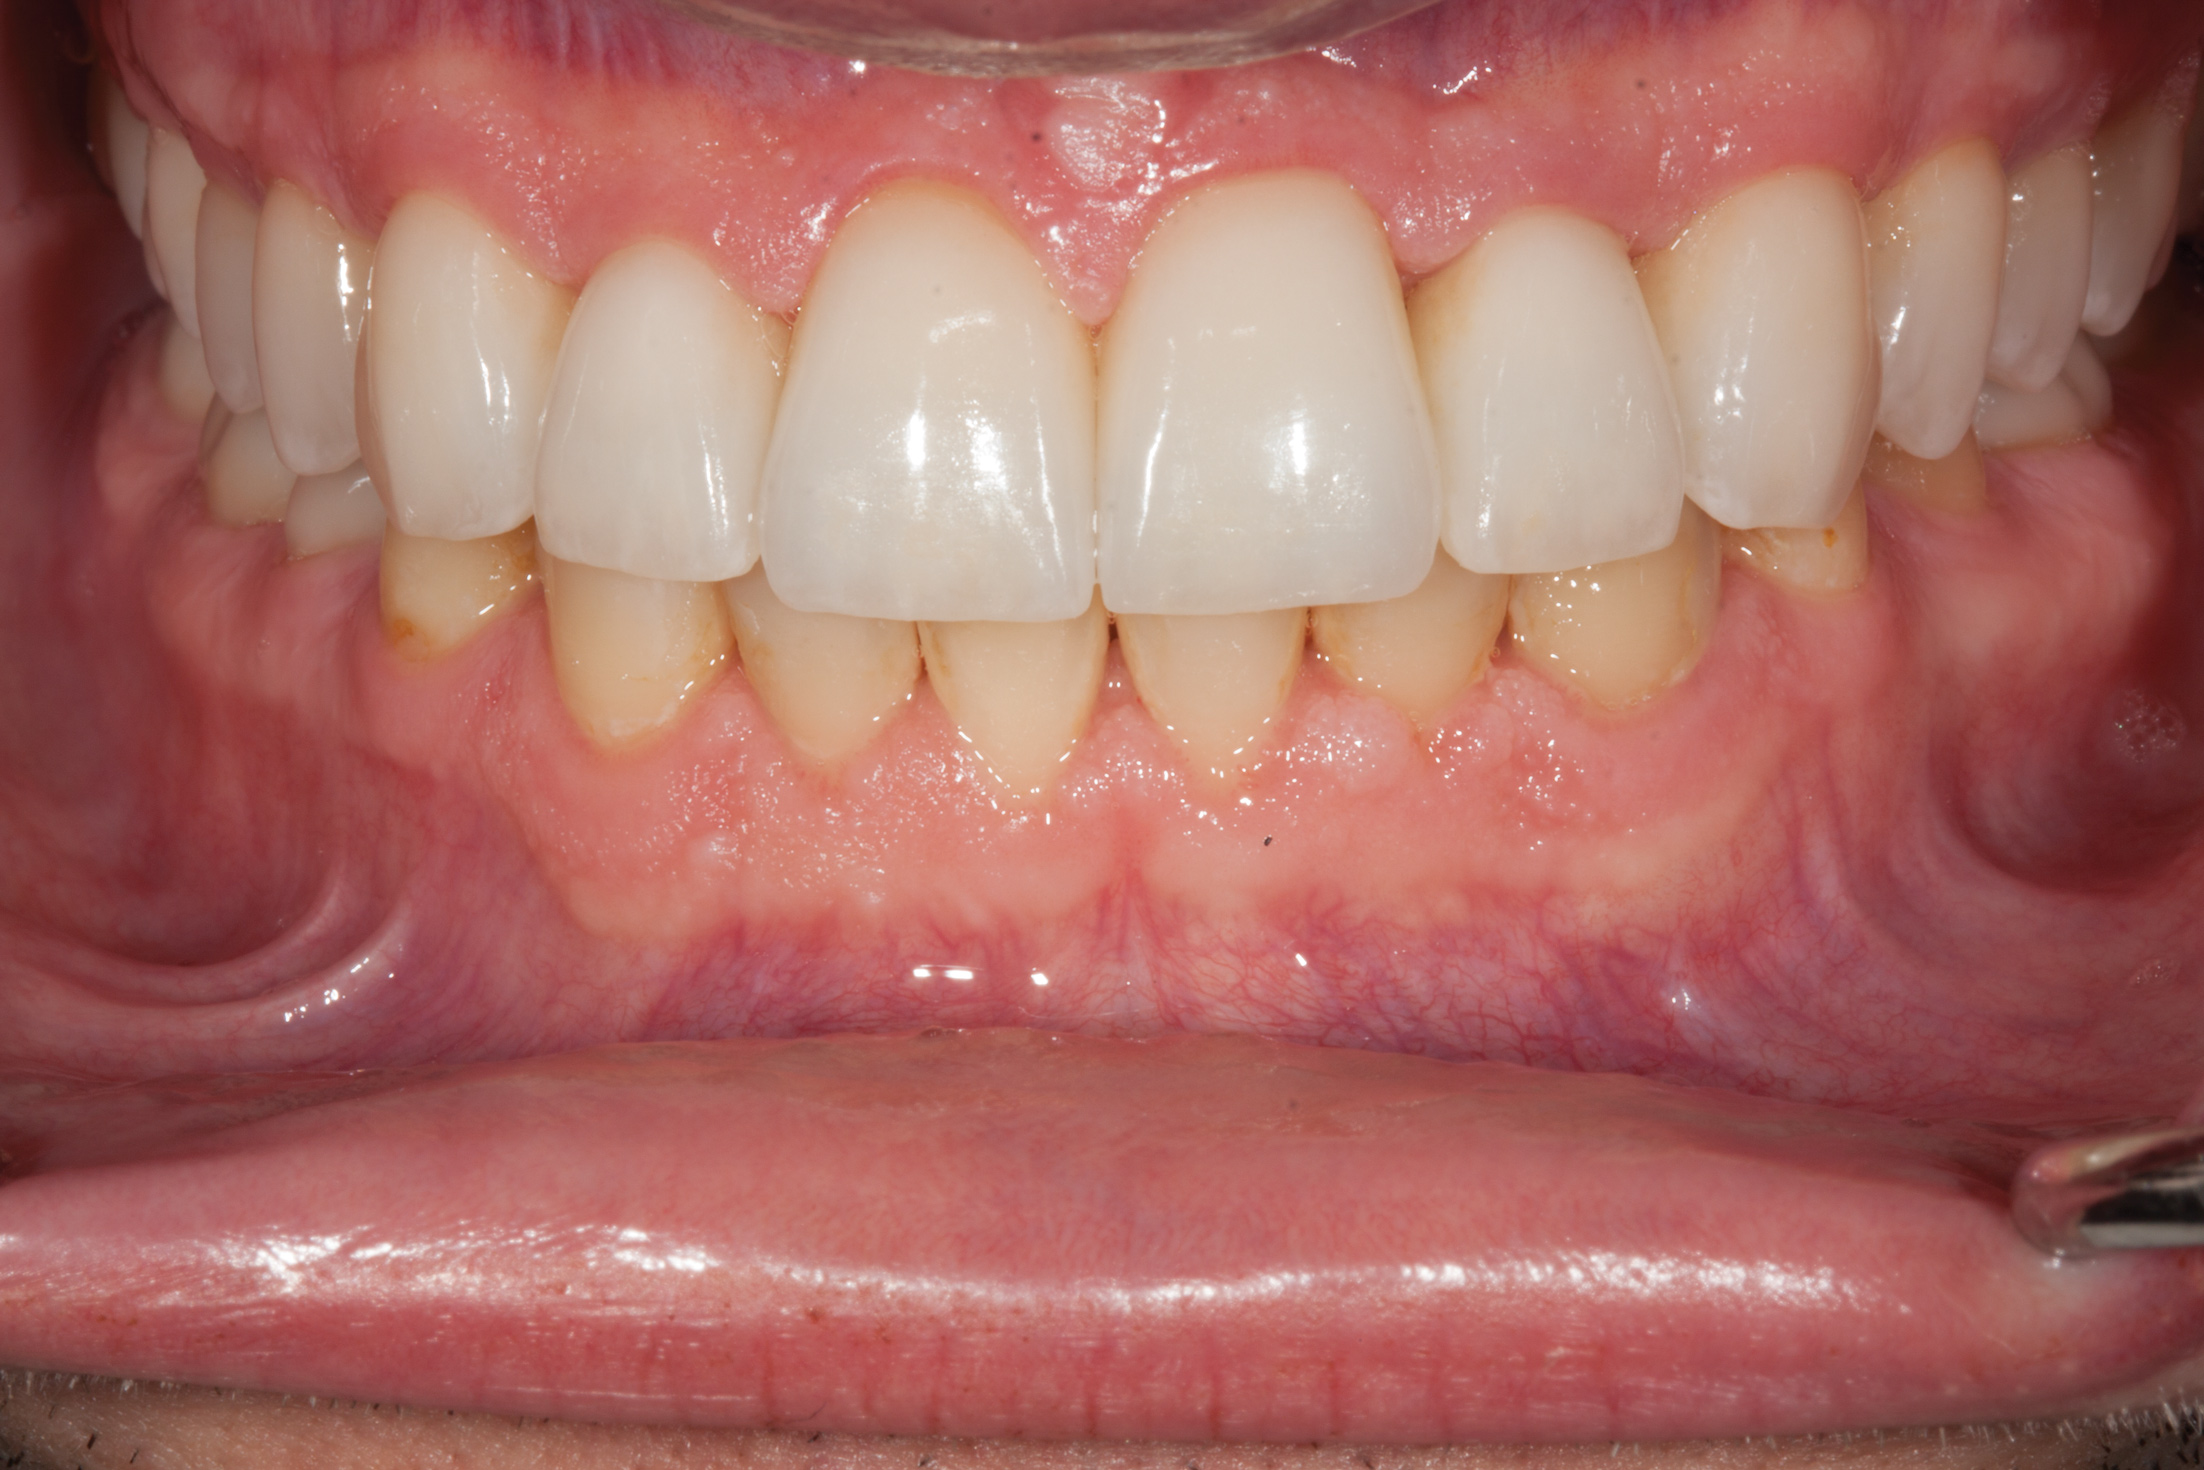

Fig 12. Prosthetic phase completion. Facial view. Note the more ideal horizontal overlap of anterior teeth and robust periodontal phenotype. Horizontal positioning of anterior teeth was enabled as a result of bone augmentation.

Figure 12